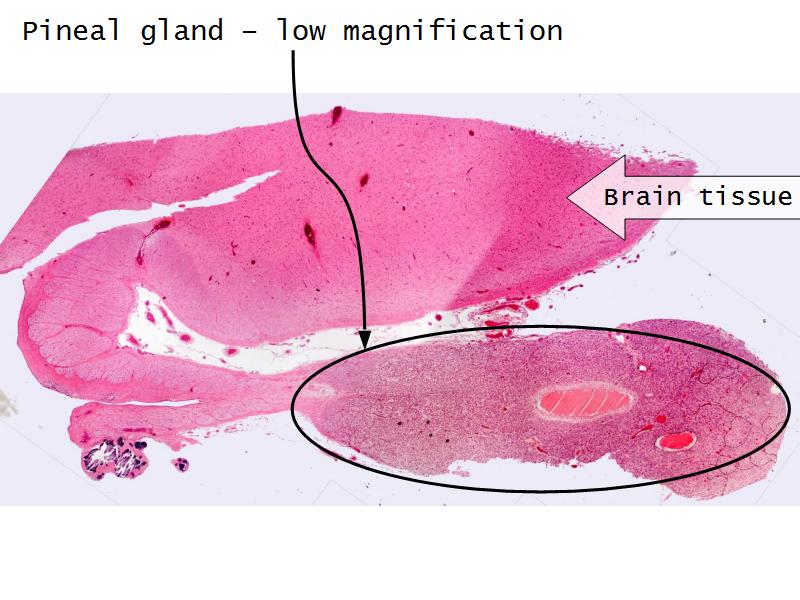

- Pineal gland

- C1: Pineal gland

- C1: Pineal gland = melatonin

- G4: Pineal gland

- G4: Pineal gland = in the midline of the brain behind the third ventricle

- Slide 34: Pineal gland

Pineal Gland